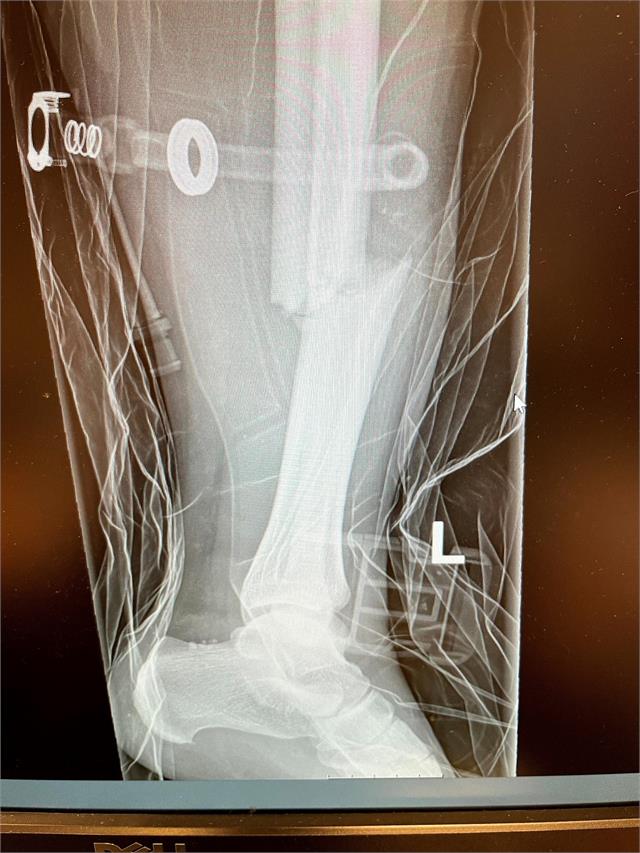

Eg skal berre lufta hundane før avreise og mange timar i bil. Eg stiller opp firhulardoningen min som er mortorlaus, og eit hint av dårlige bremser er montert. Eg selar opp 8 polarhundar med lyst til å springe sjela av seg. Eg set først to i front og følg på vidare ned mot vogna for å ferdigstille eit 8 spann på barmark. Ja du veit snøen smeltar ofte litt tidleg i vest, dessverre. Så barmarksvogna uten motor med litt dårlige bremser blir tatt i bruk. Eg stillar meg på vogna, klar for å sleppe eiergibuntane i fri dans nedover bakkane og vidare inn på vegen for å sleppa galskapen laus og komme atte med sinnet i behold og klar for rolige timar i bil for nye eventyr i vente. Lange dagar på ski, gode historiar i telta og endelig få vara ilag igjen etter ein lang periode med motstraums med covid, begrensingar og nedsteningar mot store planar og drømmar i grus. Ein tenkte livet var på ny vending og klar for leve det livet ein hadde blitt begrensa mot i så mange månedar! Første sving til høgre svingar hundane motvillig frå mi stemme rett til venstre, set firhjulardoningen på høykant og eg dengar heile foten og min tunge kropp mot asfalten. Leggen knekk tvers av. Eg held fast i vogna og hundane galoperar vidare. Eg får eit voldsomt rykk. Og fyk til værs også rett i grøfta. Knekt var foten med stor sikkerhet ettersom eg såg den stod som ein L i været.

Hundane for sin veg med vogn og vet vidare ned i vegen. Eg låg i grøfta og med ambulanse på veg. Sannsynlegvis 3 månedar med krykker og med sikkerhet ikkje tilbringa heile våren på vidda. Ein så liten avgjerelse som skal berre fort ut å lufta hundane satte meg tilbake med full funksjonell fot i eit år. 365 dagar.